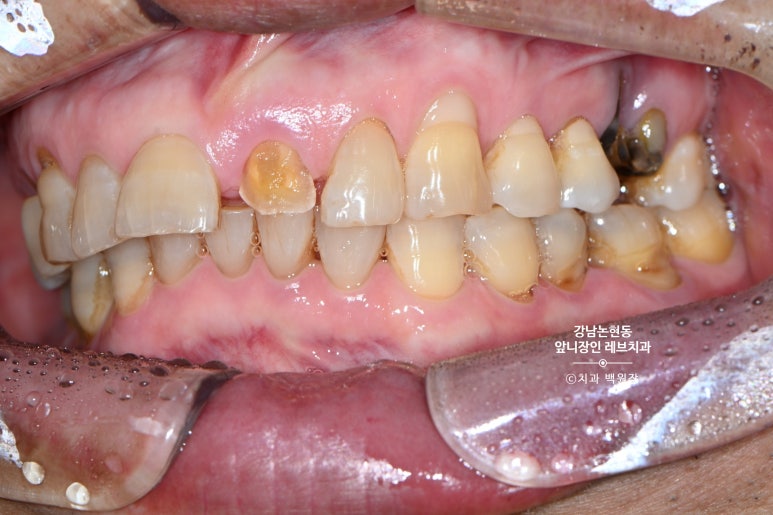

그런데 말입니다? 교합면에서 보면 꽤나 치아가 많이 남아보인단 말이지요.

입천장쪽 면에는 꽤나 치아가 남아있는것을 보실 수 있습니다.

그래서... 살려보자고 마음 먹어봤습니다.

거의 무에서 유를 창조한 셈인데요.. 저 남아있는 치아 안에 굵직한 기둥이 심겨져 있습니다.

잘 보시면 뿌리쪽에 약간 어두운 치아가 있는데, 그것이 본래 갖고 계신 자기 치아이고,

보다 밝은 색으로 대부분을 이루고 있는 부분이 기둥 (fiber post) + 레진 코어 (resin core) 입니다.

씹는 면에서 보면 꽤나 깊이 치아의 경계가 형성된 것도 확인할 수 있으실겁니다.